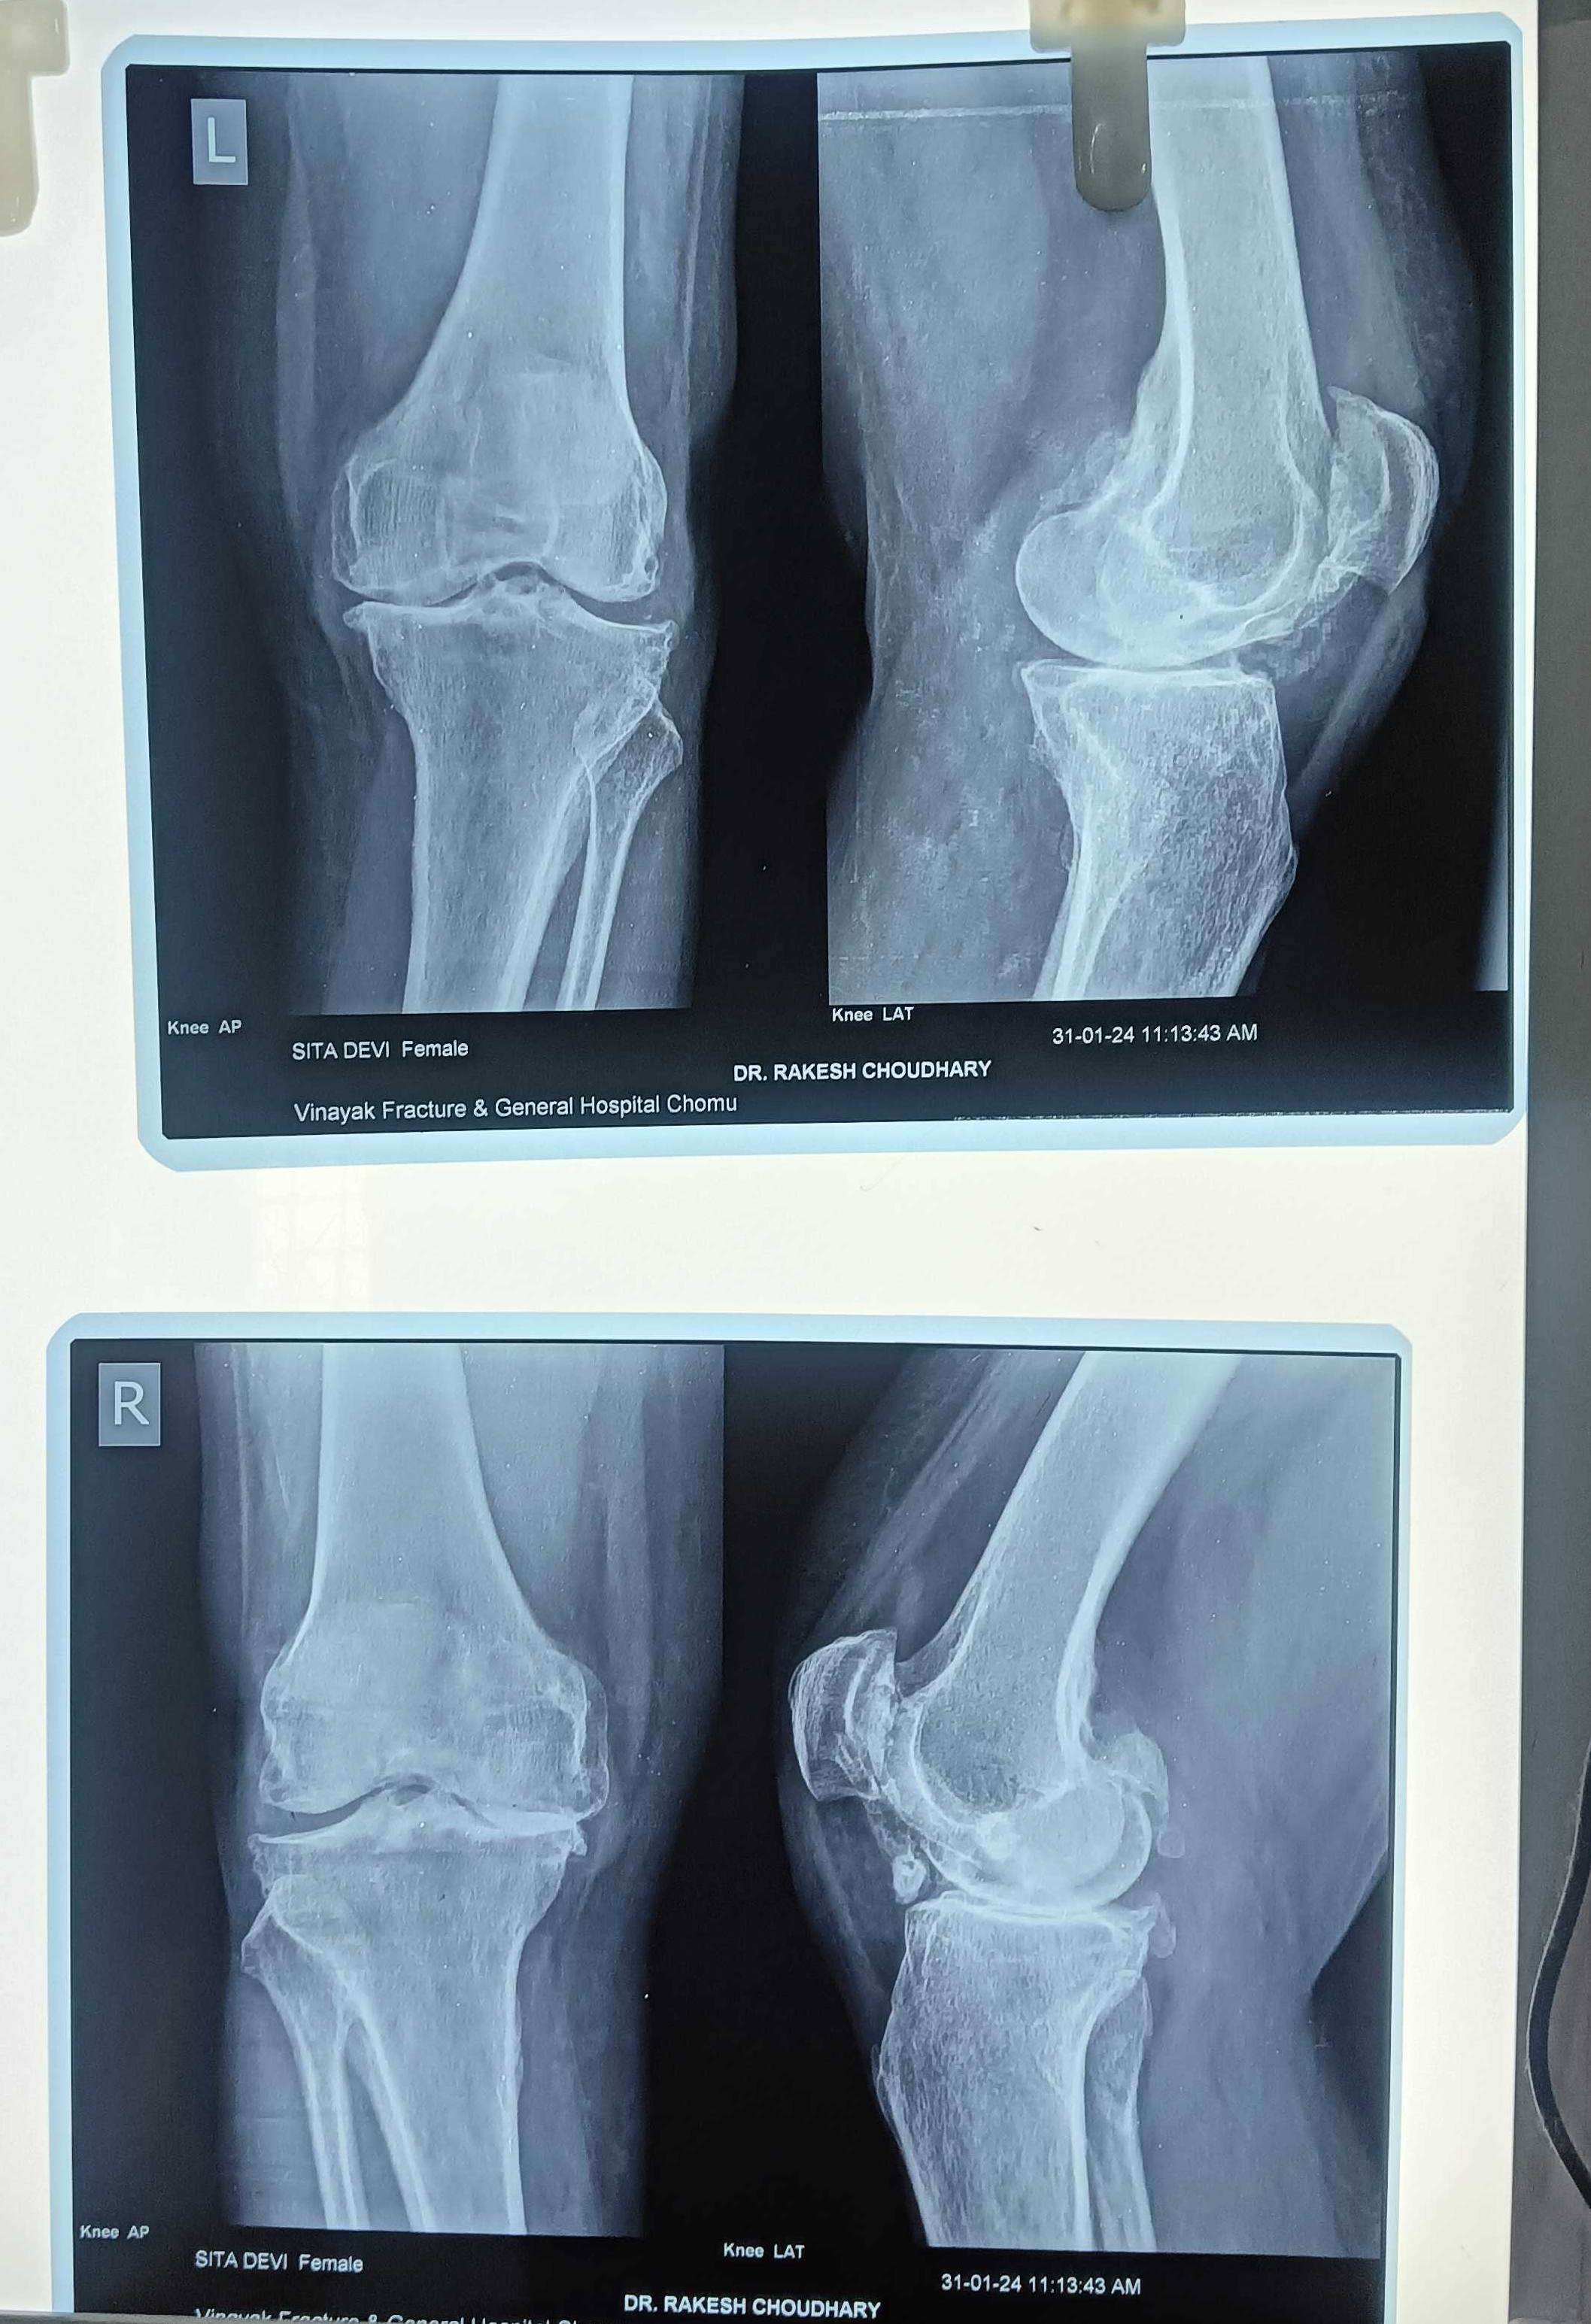

सबसे बेस्ट इंप्लांट कौनसा रहेगा कोनसा मॉडल रहेगा सीमेंटेड या सीमेंटलेस या फिर हाइब्रिड पूरी जानकारी दीजिए

क्या ये मुख्यमंत्री आयुष्मान आरोग्य योजना में कवर है या पैड है कृपया रिप्लाई जरूर दीजियेगा। क्या इसके लिए गोल्ड नी इंप्लांट की नीड है

8-10 साल से ये समस्या है टैबलेट भी काम करना बंद कर दी।